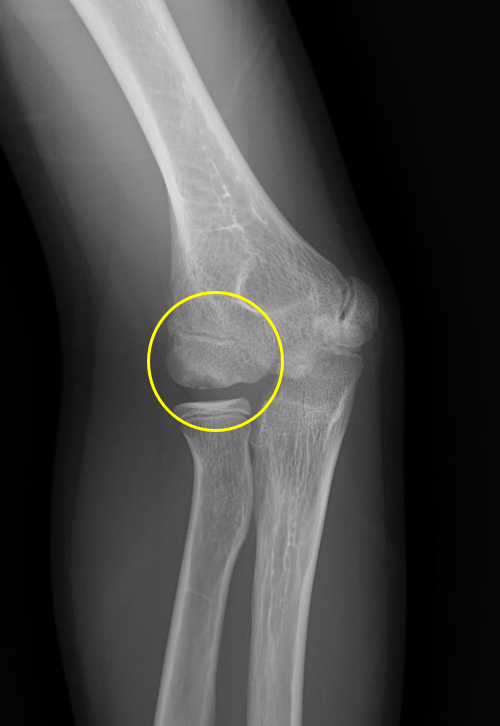

肘の離断性骨軟骨炎(以下:OCD:osteochondritis dissecans)は上腕骨小頭という部位に好発することが多いです。

OCDは成長期の代表的なスポーツ障害であり、野球などといった投球・投擲動作を行うスポーツ選手で投球側に発生することが多いです。大半は10-12歳で発症し成長期における有病率は2-3%と頻度は少ないが進行するとスポーツにみならず、日常生活お支障をきたすことが多い怪我です。そのため、早期発見・早期治療が重要となります。

一般的にレントゲンによる分類が用いられ、初期・進行期・終末期に分けられます。

OCDを発見するにはレントゲンや超音波検査で上腕骨小頭軟骨下骨の状態を観察します。

軟骨下骨の不整像が軽微か不明の場合はMRI検査を行いOCDの確定診断を行います。

2024年5月、当院受診。レントゲン撮影をして離断性骨軟骨炎と診断されてリハビリ開始。